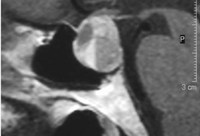

- La anomalía de morning glory con frecuencia se presenta asociada al encefalocele transesfenoidal (Figura 7). Éste también se manifiesta junto con discos ópticos displásicos y anomalías retinocoroideas infrapapilares en forma de V o de reguero. La enfermedad de Moyamoya es una vasculitis cerebral rara que también se asocia a esta anomalía papilar.

Figura 7. Anomalía de morning glory con encefalocele transesfenoidal asociado